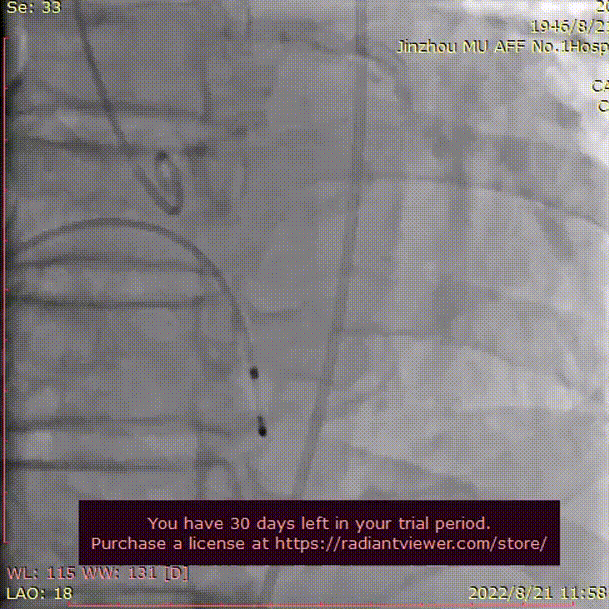

弓部及入路评估

入路血管:双侧髂股动脉明显扭曲,双侧髂总及弓部散在钙化,双侧入路血管直径良好。

双侧股髂动脉明显扭曲,双侧髂总及弓部散在附壁钙化,双侧入路血管直径良好,常规选取右侧股动脉作为主入路,左侧为辅入路;